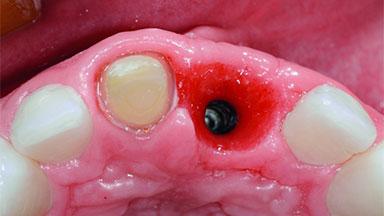

Replacement of an Ankylosed Upper Left Central Incisor: Bone Augmentation and Socket Grafting, Late Placement of an RC Bone Level Implant

Bone Augmentation Horizontal|Simultaneous|Staged

Augmentation Materials Autogenous chips|Xenogenous